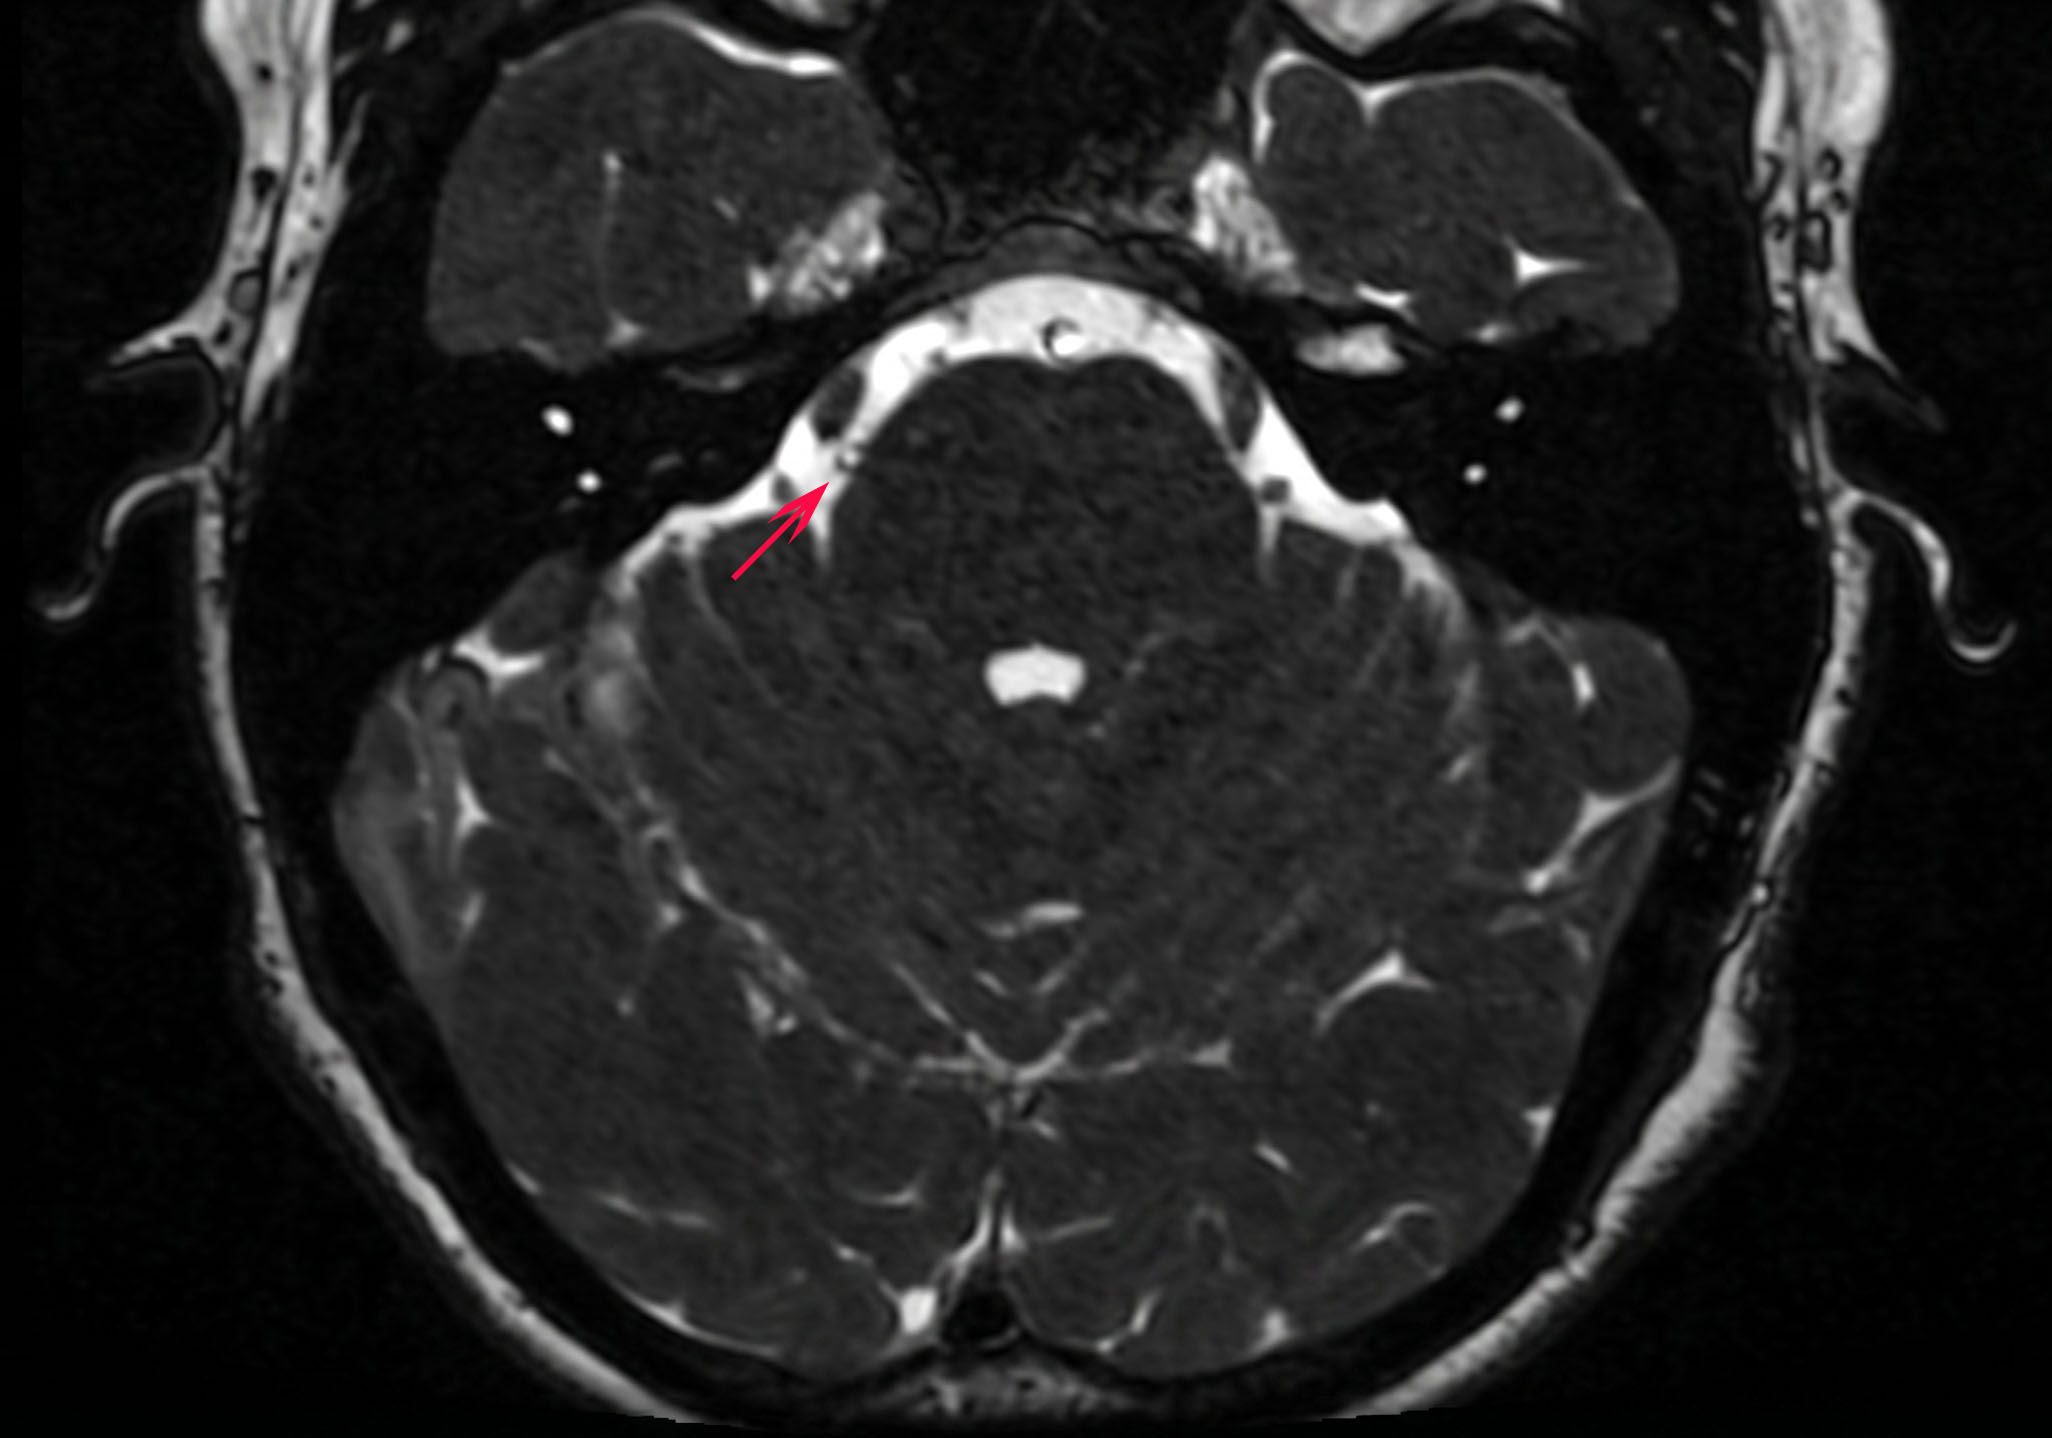

Nello studio RM dedicato al trigemino, la root entry zone è il punto che merita maggiore attenzione quando si cerca un possibile conflitto neurovascolare. Le sequenze ad alta risoluzione permettono di valutare se un’ansa arteriosa o, meno spesso, una struttura venosa si trovi in rapporto stretto con il nervo proprio in questa sede.

Non basta però vedere un vaso vicino al trigemino: conta la sede precisa del rapporto, la concordanza con il lato del dolore e l’eventuale presenza di una deformazione del nervo. È qui che la semplice descrizione radiologica deve trasformarsi in interpretazione clinica.

Nello studio RM ad alta risoluzione la root entry zone è il tratto più importante da analizzare quando si sospetta un conflitto neurovascolare.